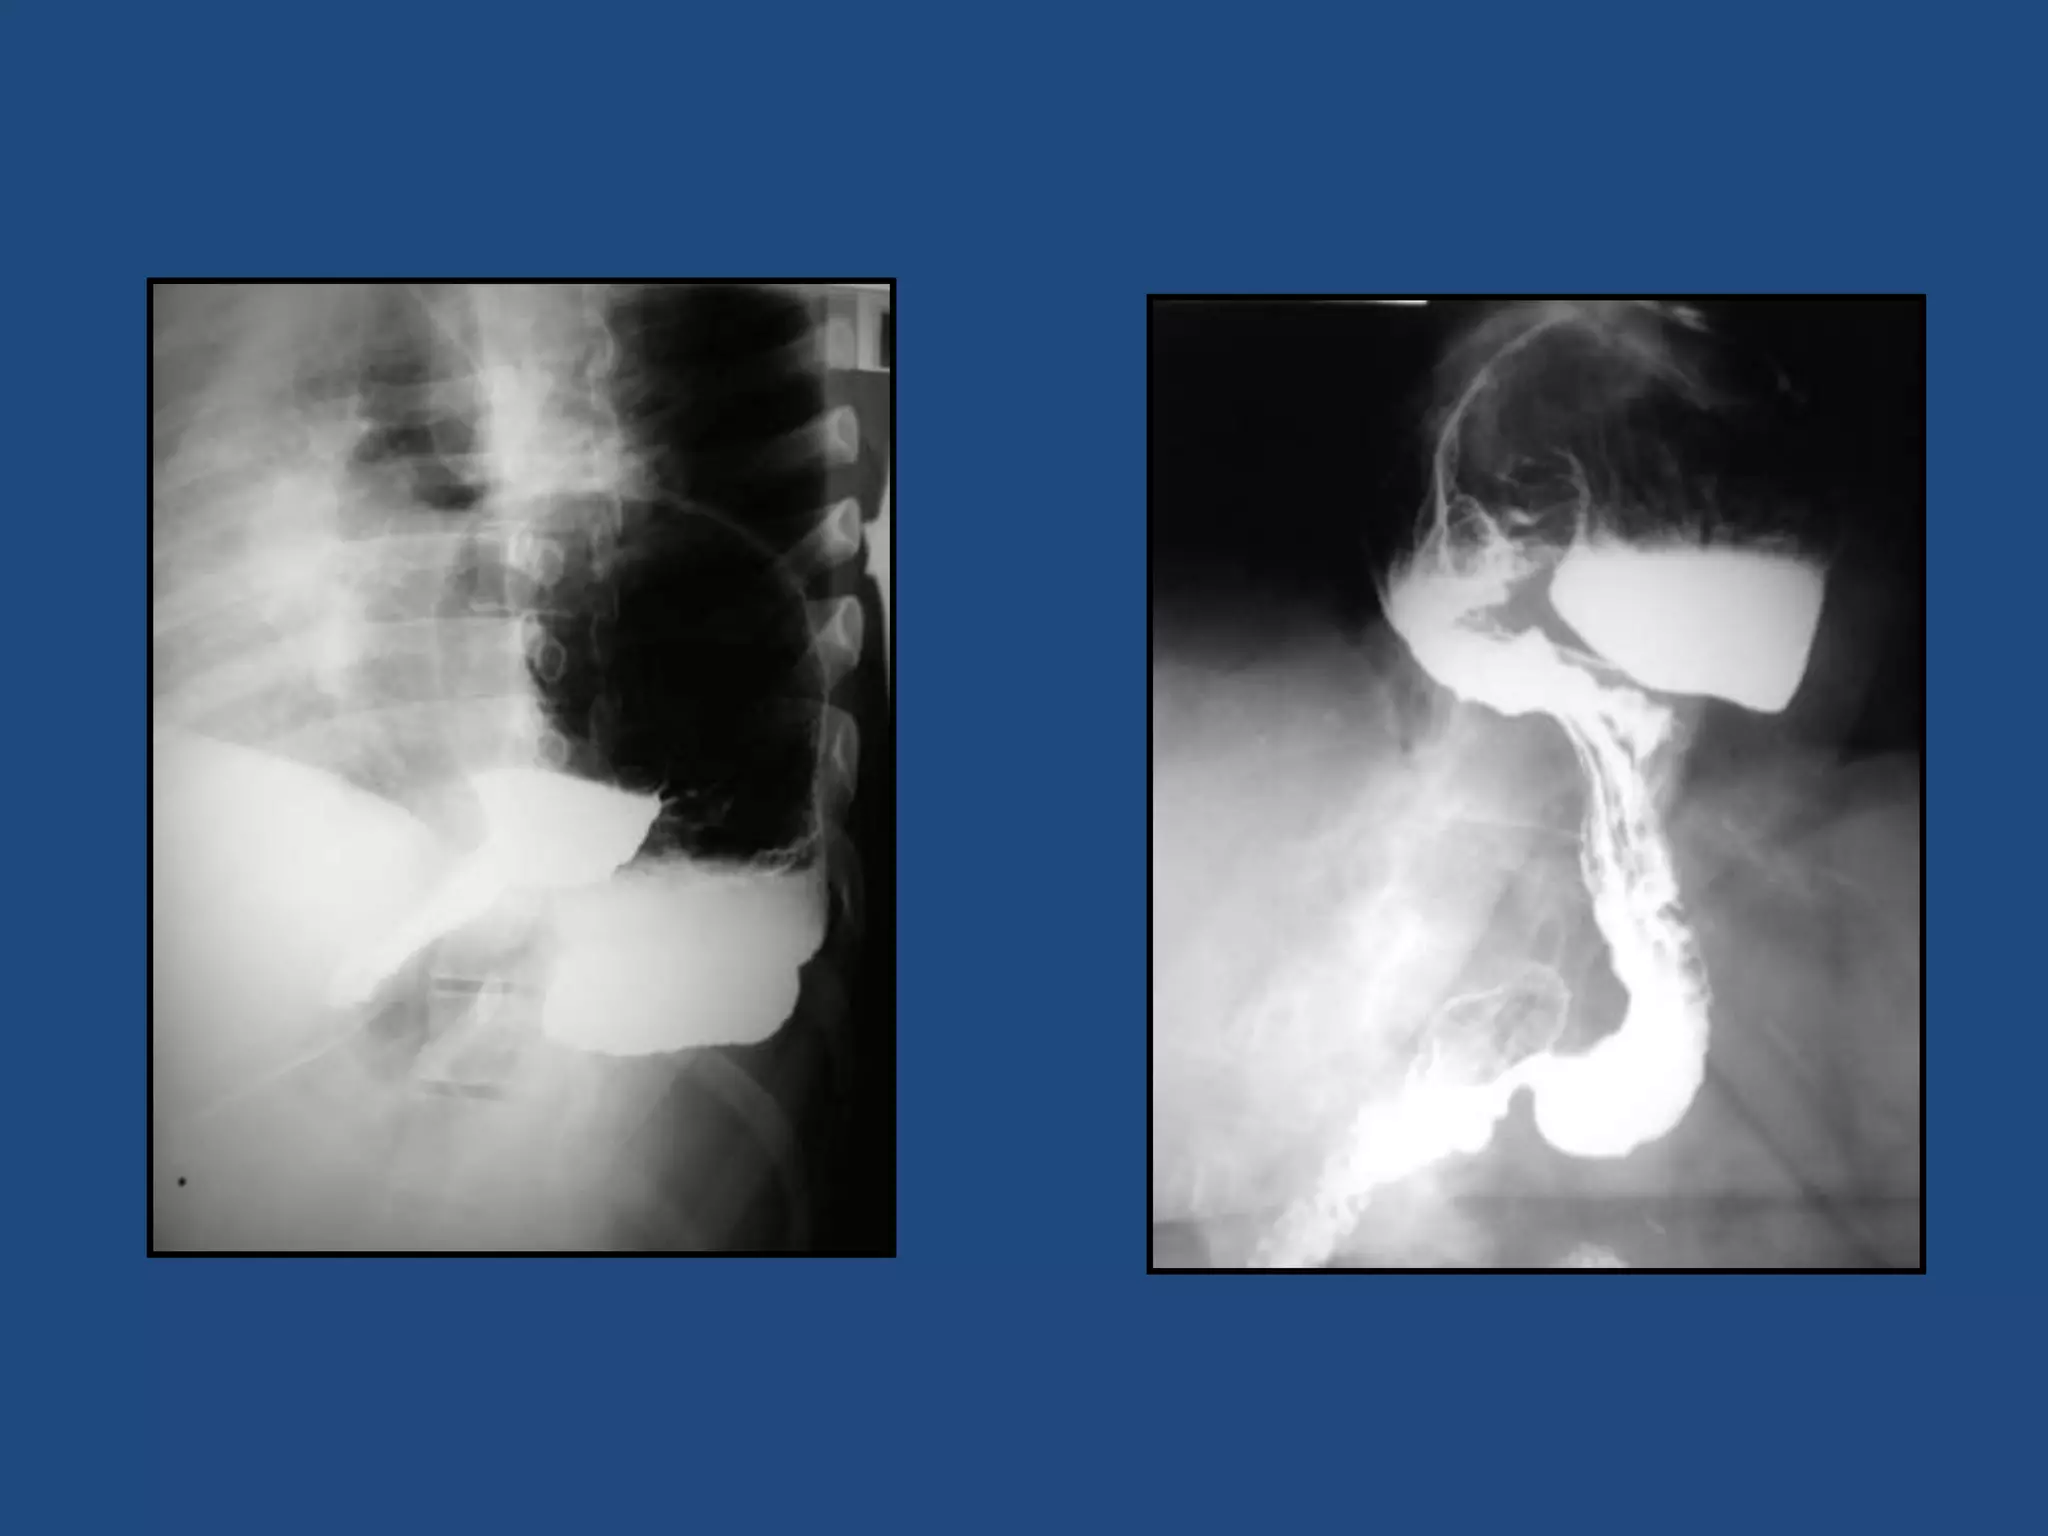

COMPLICACIONES

• HEMORRAGIA (más frecuente DUODENAL)

• PERFORACION

- 5-10% (más frecuente DUODENAL)

- A CAVIDAD LIBRE/ ORGANOS VECINOS

• OBSTRUCCION

- NIVEL PILORICO DUODENAL

RX SIMPLE

ABDOMEN

SOSPECHA DE COMPLICACIÓN

PERFORACIÓN = NEUMOPERITONEO

ESTÓMAGO: ÚLCERA GASTRODUODENAL